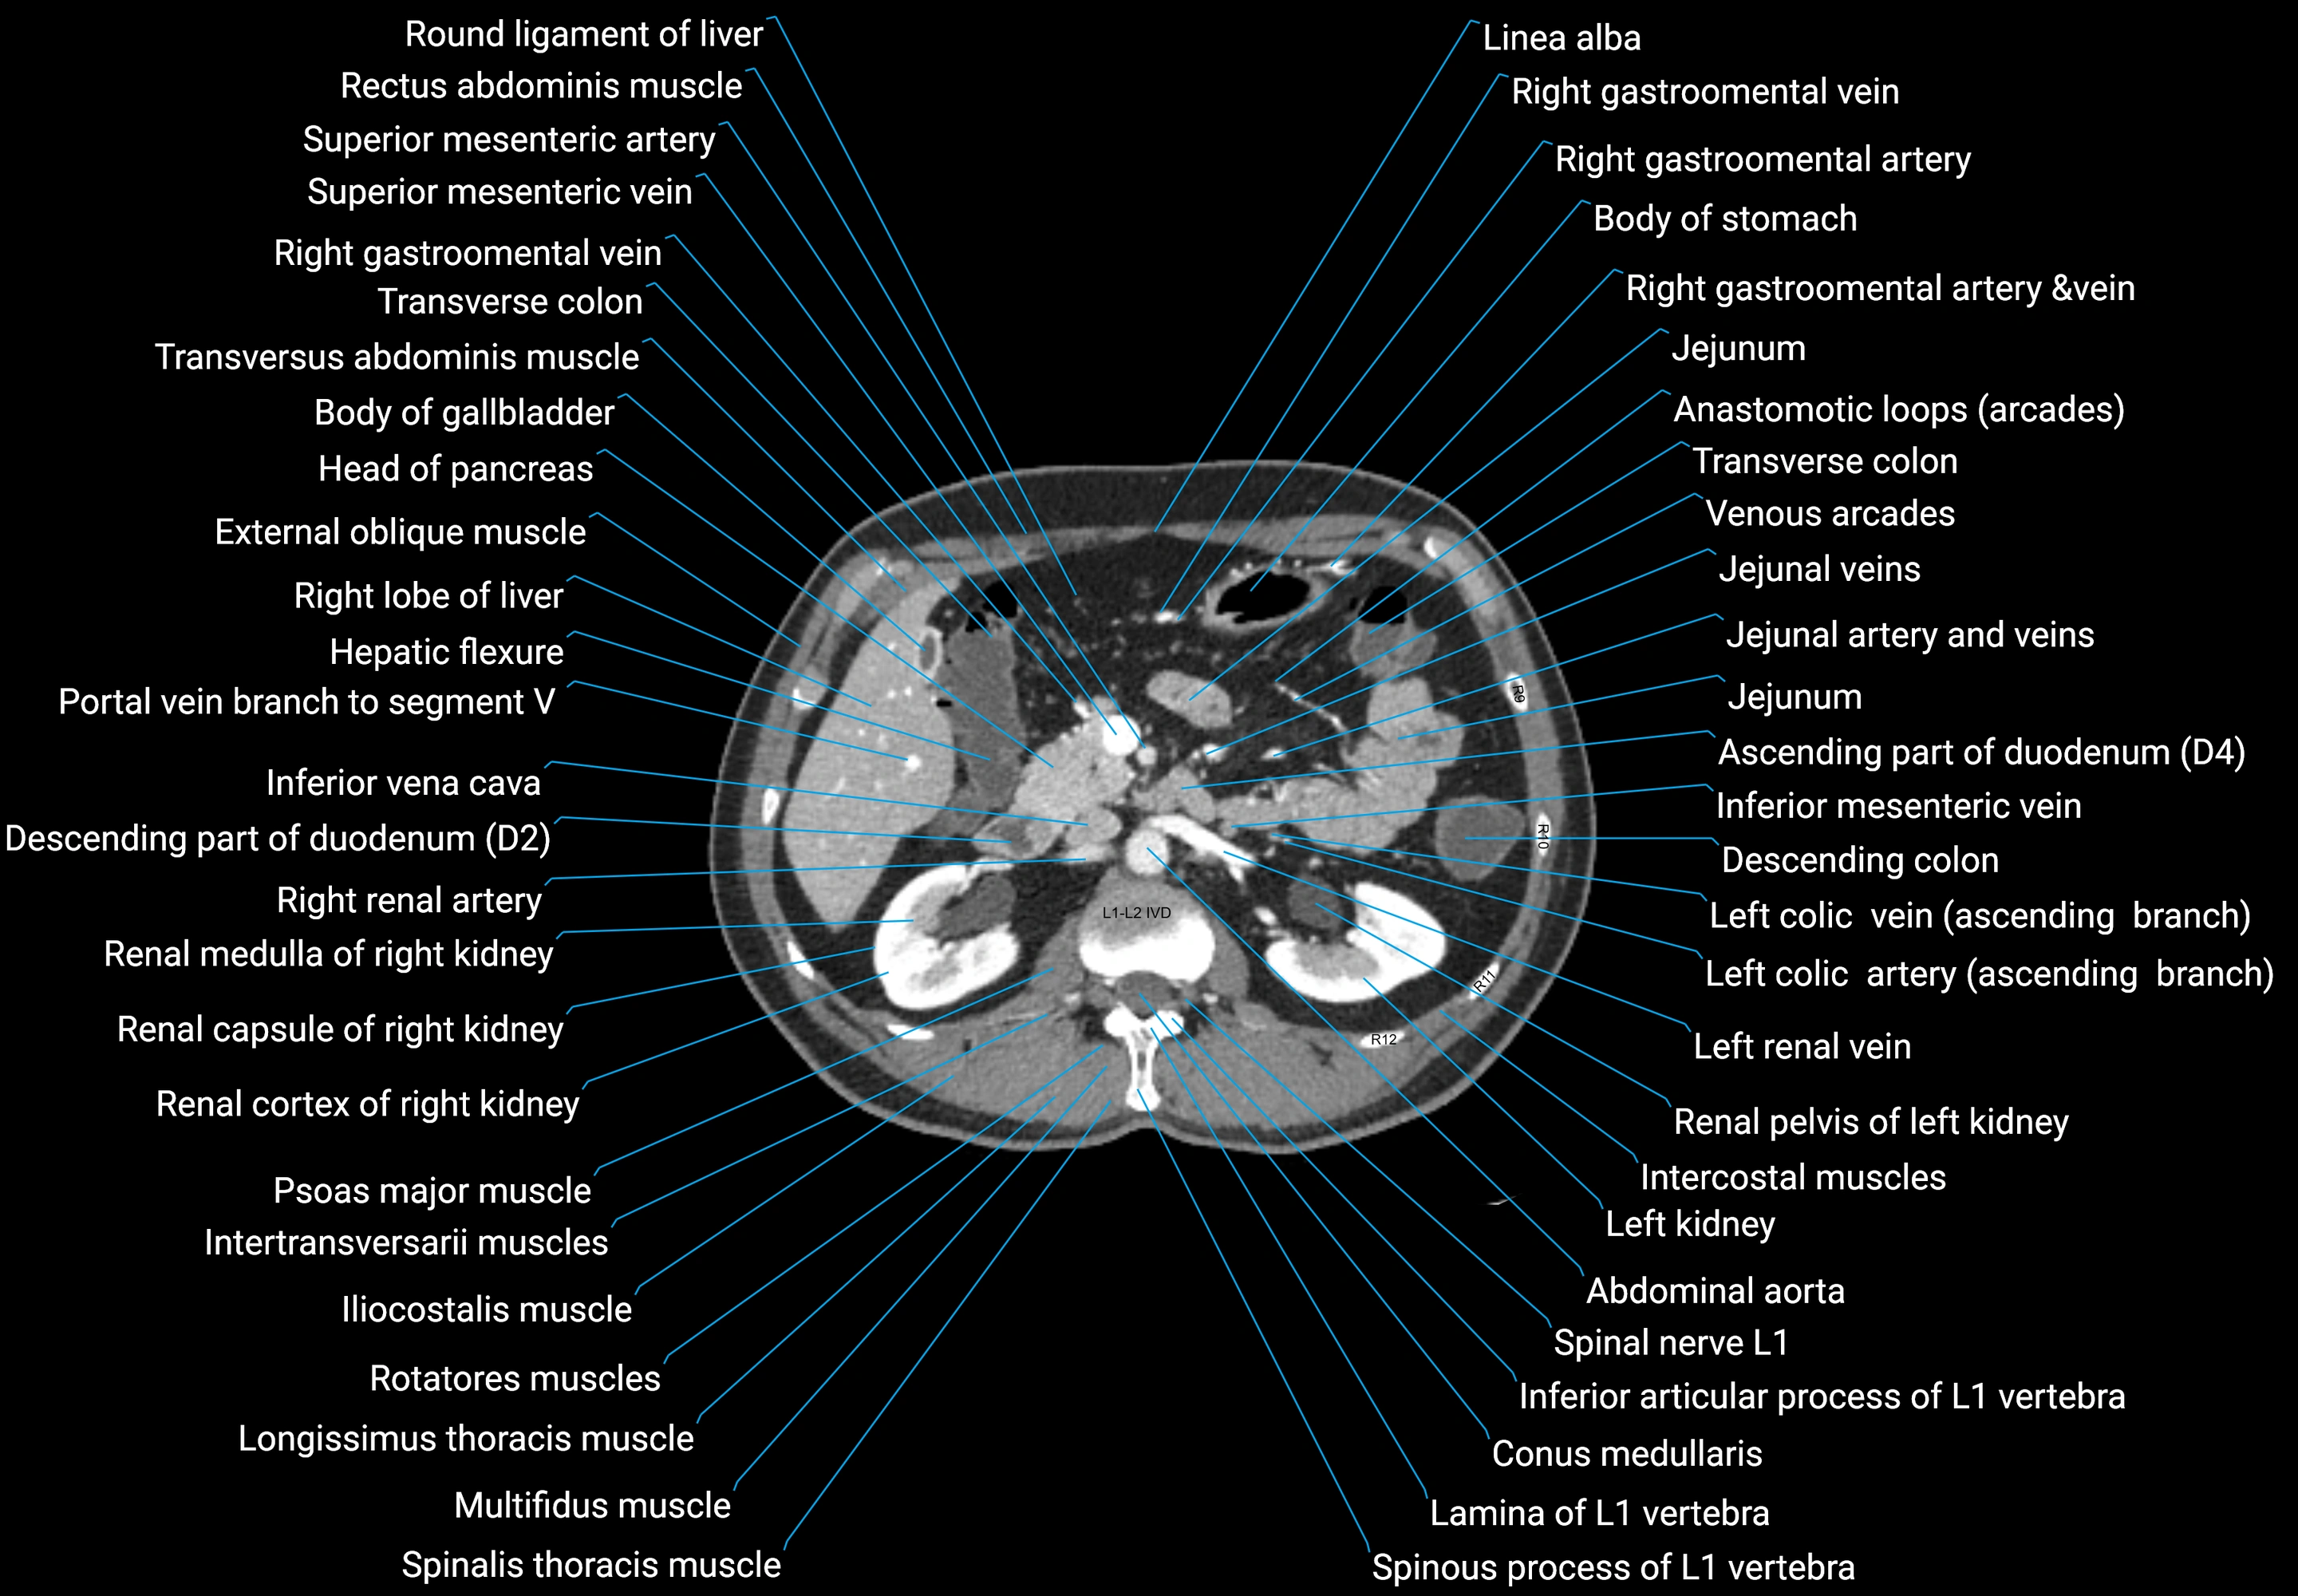

CT images